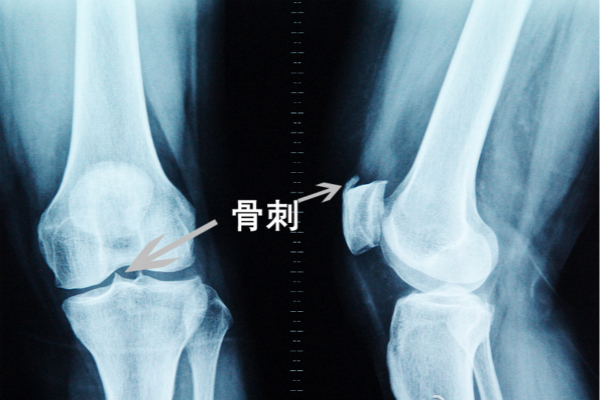

骨質(zhì)增生算是骨科常見病,是一種慢性、進(jìn)展性關(guān)節(jié)病變,主要累及手的近節(jié)和末節(jié)指間關(guān)節(jié)、脊柱和髖、膝、踝關(guān)節(jié)等,以關(guān)節(jié)疼痛、變性和活動受限為特點(diǎn)。關(guān)節(jié)活動尤其是負(fù)重時疼痛加劇,休息后減輕或緩解

骨質(zhì)增生疼起來很難受,尤其是老年人,經(jīng)常聽到外婆呀,奶奶呀,腿疼的受不了,那么這里就建議選擇保守改善最直接有效的王九正貼,王九正黑膏藥是利用現(xiàn)代生物科技,活化萃取中藥中的有效成分,利用遠(yuǎn)紅外磁療貼的放射性吸收療法,把中藥中的有效成分快速滲透到您的疼痛部位,消除內(nèi)部無菌性炎癥,同時,讓骨刺變得圓潤,不在刺破骨頭,從而去除疼痛,加上后期適當(dāng)?shù)目祻?fù)鍛煉,就可以起到很好的治改善果!